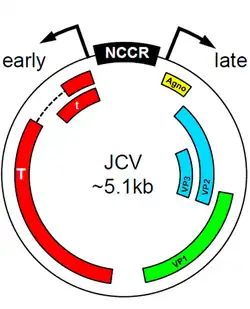

Human polyomavirus 2 found in the central nervous system of PML patients almost invariably have differences in promoter sequence to Human polyomavirus 2 found in healthy individuals. It is thought that these differences in promoter sequence contribute to the fitness of the virus in the CNS and thus to the development of PML.[6] Certain transcription factors present in the early promoter sequences of Human polyomavirus 2 can induce tropism and viral proliferation that leads to PML. The Spi-B factor was shown to be crucial in initiating viral replication in certain strains of transgenic mice.[16] The protein encoded by these early sequences, T-antigen, also plays a key role in viral proliferation,[17] directing the initiation of DNA replication for the virus as well as performing a transcriptional switch to allow for the formation of the various capsid and regulatory proteins needed for viral fitness. Further research is needed to determine the exact etiological role of T-antigen, but there seems to be a connection to the early initiation of the active virus from its archetypal dormant state.

Human polyomavirus 2 also appears to mediate encephalopathy, due to infection of cortical pyramidal neurons (CPN) and astrocytes.[20] Analysis of the JCV CPN variant revealed differences from JCV GCN: no mutations were found in the VP1 coding region; however, a 143–base-pair deletion was identified in the agnogene, coding for a 10–amino-acid truncated peptide, which is believed to mediate CPN tropism. Additionally, analysis of the subcellular localization of JC CPN virions in nuclei, cytoplasm, and axons suggests that the virus may travel through axons to increase infectivity.[20]